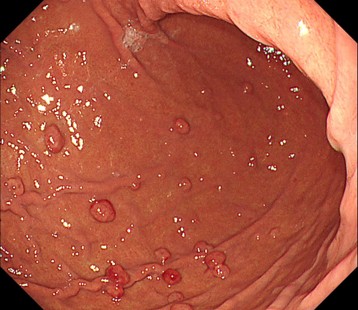

当クリニックで発見されたピロリ未感染微小胃癌

①白色光像

背景粘膜は多発胃底腺ポリープと、萎縮性変化の無いピロリ未感染胃粘膜

②白色光像

前庭部小弯に褪色調の平坦病変

➂NBI(狭帯域光観察)併用非拡大観察

同部位に白色調変化あり

④NBI併用拡大観察

病変内は異型血管を認めず、窩間部の開大所見あり

生検病理: Group 5 (印環細胞癌)

専門病院へ紹介し、ESDで一括切除

病理診断 0-IIb,Adenocarcinoma, 4mm, pT1a(M), ly0 ,v0 ,HM0 ,VM0

(早期胃癌 粘膜内癌 脈管・リンパ管侵襲なく治癒切除)